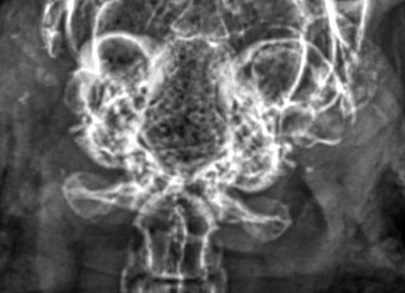

Computertomographie (CT), Digitale Volumentomographie (DVT)

Optimal zur Feststellung von pathologischen Veränderungen bereits im Anfangsstadium, zur exakten Beurteilung der verschiedenen Ohrabschnitte, des Ausmaßes und der Lokalisation der Entzündung ist die Computertomographie. Darunter fällt auch die sogenannte digitale Volumentomographie (DVT), ein besonders hochauflösendes CT.

CTs sind nur in Kliniken und größeren Praxen möglich, und leider bieten noch nicht alle die Möglichkeit eines "Wach-CTs" an, obwohl dieses gerade bei geschwächten Tieren einer Narkose unbedingt vorzuziehen ist.

Bei den meisten Kaninchen ist die Durchführung eines Wach-CT völlig unproblematisch; die Tiere werden dafür in eine kleine Kiste gesetzt, die anschließend sorgfältig mit Decken ausgepolstert wird, sodass nahezu keine Bewegungen mehr möglich sind. Eine Abdunklung des Raumes trägt zusätzlich dazu bei, dass die Tiere ruhig atmen und stillhalten.

Anschließend fahren sie in der Kiste durch den Computertomographen, was nur wenige Sekunden dauert. Die meisten Kaninchen halten für diese kurze Zeitspanne völlig still, da die Dunkelheit und die Enge ihnen ein "Höhlengefühl" und somit Sicherheit vermitteln.

Vor allem vor einer (möglicherweise) geplanten Operation lohnt es sich, eine Klinik ausfindig zu machen, die CTs am wachen Kaninchen anbietet, und ggf. auch eine etwas längere Anfahrt in Kauf zu nehmen. Alternativ kann vereinbart werden, dass das CT in Narkose erfolgt und das Kaninchen gegebenenfalls im unmittelbaren Anschluss operiert wird. Der Tierarzt muss in diesem Fall unbedingt auf Kaninchen ("Heimtiere", "Kleinsäuger" - NICHT Kleintiere (= Katzen & Hunde)!) spezialisiert sein.

Die Qualität von Wach-CTs wird häufig zu Unrecht angezweifelt. Gegner argumentieren, dass die Aufnahmen generell verwackelt oder unscharf seien, da ein waches Kaninchen nicht stillsitzen würde und mit einer Atmungsunschärfe zu rechnen sei.

Hier spielen das Management und die Erfahrung des behandelnden Tierarztes eine entscheidende Rolle: Das Kaninchen muss mit viel Fingerspitzengefühl bequem und gerade in der Box positioniert werden, und jeglicher Hohlraum muss durch Decken, Tücher etc. ausgefüllt werden. Die wenigsten Kaninchen starten hier "Befreiungsversuche", da die eigentliche Untersuchung nur wenige Sekunden dauert und das Überraschungsmoment währenddessen die Oberhand hat.

Weiterhin ist es von großer Bedeutung, dass das Kaninchen während der Untersuchung möglichst keinen Stress hat und dementsprechend ruhig atmet. Hierfür empfiehlt es sich, es vor dem CT - ggf. in einem separaten, ruhigen Raum - zunächst in Ruhe "ankommen" und akklimatisieren zu lassen. Dies sollte für das Zeitmanagement der Praxis kein Problem darstellen, da auch eine Narkose nie unmittelbar nach der Ankunft erfolgen sollte, sondern erst, wenn das Kaninchen sich vom Fahrtstress erholt hat.

Korrekt ist natürlich, dass ein narkotisiertes Kaninchen zwangsläufig langsamer atmet als ein waches. Aber atmen tut es natürlich auch - eine hundertprozentige Schärfe ist folglich beim lebenden Tier nie möglich. Bei einem entspannten wachen Kaninchen kann die Qualität eines Wach-CTs durchaus mit der eines CTs in Narkose mithalten (DVT eingeschlossen). Und sollte es doch zu einer unerwünschten Bewegung kommen, wird ein gewissenhafter Tierarzt das CT unmittelbar im Anschluss einfach wiederholen.